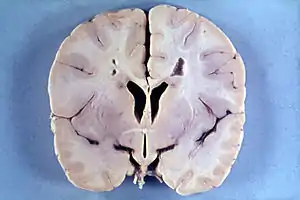

| Brain of a 4-year-old boy with Alexander disease showing macroencephaly and periventricular leukomalacia (note brownish discoloration around the cerebral ventricles) | |